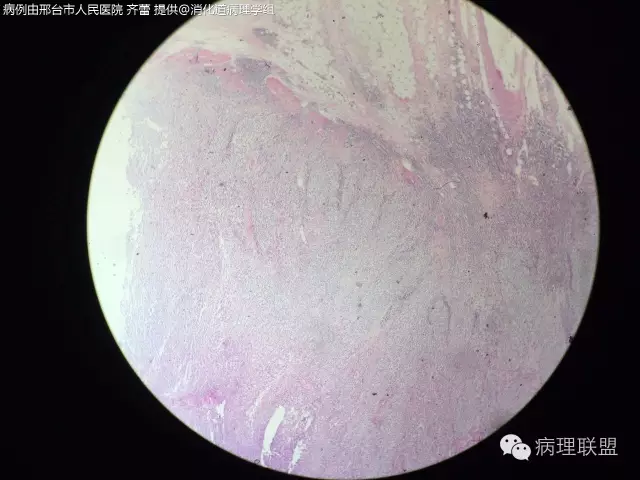

【罕见病例】F/52 小肠肿物-胃肠道恶性神经外胚瘤(MGNET)

胃肠道恶性神经外胚瘤(MGNET).

@齐蕾 感谢分享精彩病例,您的组化做的很全面了,诊断和鉴别诊断标记基本都在了。我也是前段时间碰到过一例有点印象。加上您这一例加深了对该肿瘤形态学诊断及鉴别诊断的认识

@齐蕾,非常少见的好病例!同意周老师意见,最好再加做一下分子检测(FISH或PCR)证实一下有无EWSR1重排,IHC的SOX10阳性也有帮助。除了图中所示形态特点外,这类肿瘤中还可见散在的多核巨细胞,不妨再找找,show给大家看看

非常好的病例。但因发生于腹腔内脏器官,诊断为弥漫型节细胞神母应更妥。

因为S100、GFAP阳性。